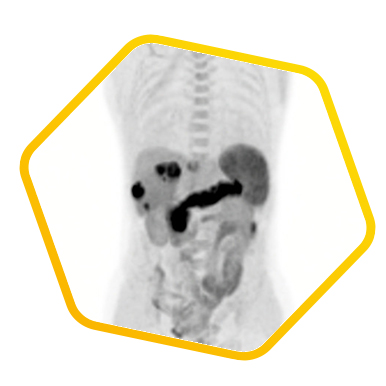

Dual tracer PET/CT (F-18 FDG and Ga-68 DOTATATE) are used for the metastatic evaluation of neuroendocrine tumor.

![]() [Ga-68] DOTATATE |